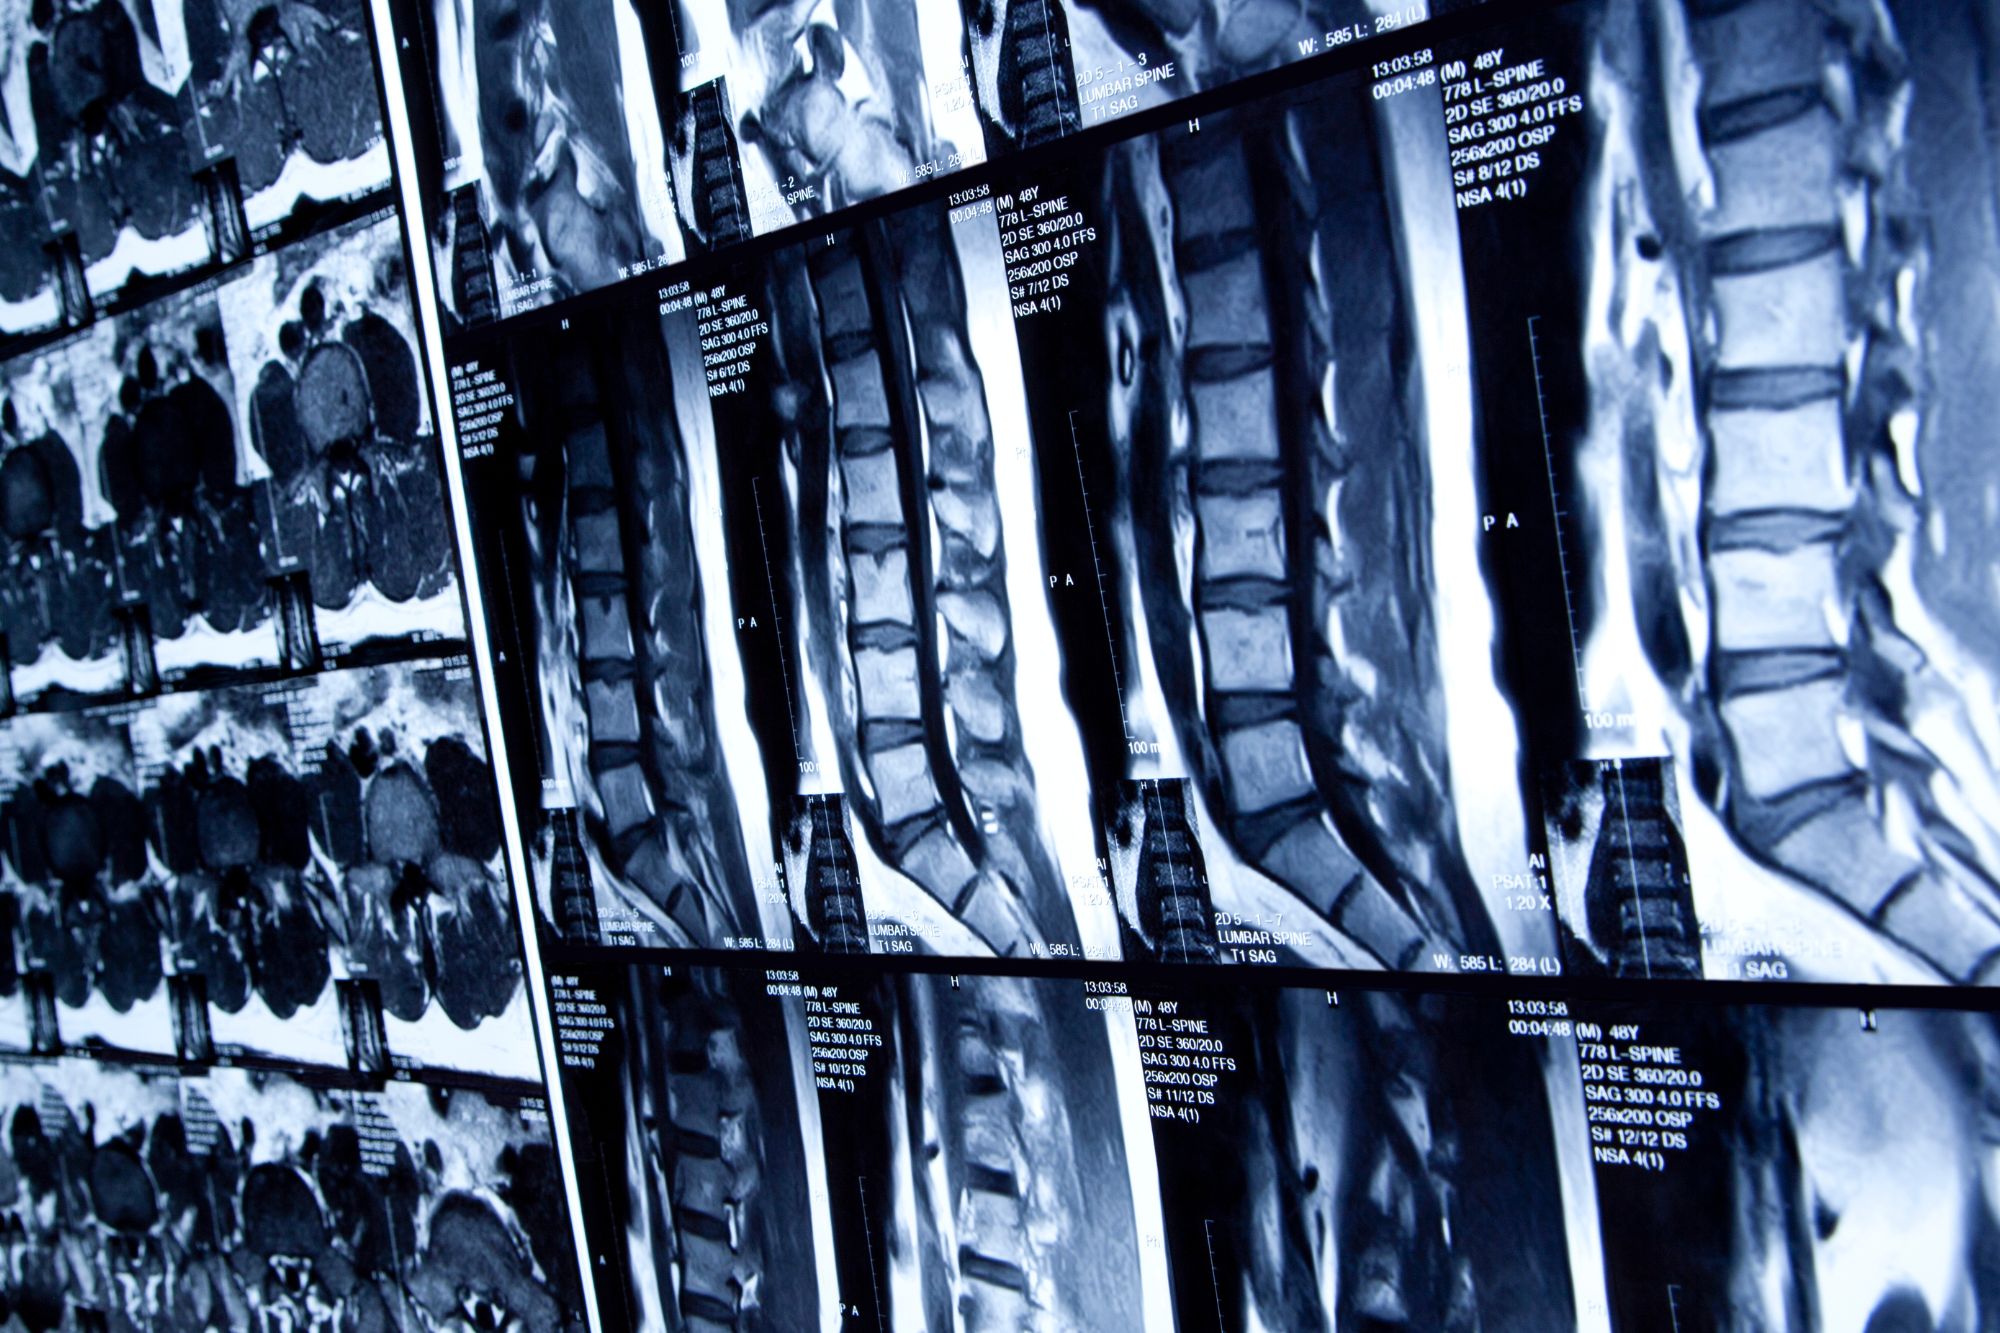

Η σπονδυλική στήλη αποτελεί έναν από τους πιο σημαντικούς και ευαίσθητους τομείς του ανθρώπινου οργανισμού, καθώς υποστηρίζει το σώμα, προστατεύει το νωτιαίο μυελό και επιτρέπει την κινητικότητα. Παρά τη σημαντικότητα της, η σπονδυλική στήλη είναι επιρρεπής σε αρκετές παθήσεις, οι οποίες μπορούν να προκαλέσουν έντονο πόνο και δυσλειτουργία. Η ανάγκη για έγκαιρη διάγνωση και θεραπεία καθίσταται αναγκαία, και σε πολλές περιπτώσεις απαιτεί τη συμβολή ειδικών, όπως ο νευροχειρουργός. Παρακάτω παρουσιάζονται οι πιο κοινές παθήσεις της σπονδυλικής στήλης.

Η δισκοκήλη είναι μια από τις πιο συνηθισμένες παθήσεις της σπονδυλικής στήλης και συμβαίνει όταν ένας από τους μεσοσπονδύλιους δίσκους, οι οποίοι λειτουργούν ως “μαξιλαράκια” ανάμεσα στους σπονδύλους, προεξέχει ή παρεκκλίνει από τη θέση του. Αυτό μπορεί να προκαλέσει πίεση στις νευρικές ρίζες, με αποτέλεσμα πόνο, μουδιάσματα ή αδυναμία στα άκρα. Ο νευροχειρουργός είναι συχνά αυτός που αναλαμβάνει την περίπτωση σε προχωρημένα στάδια, όταν η συντηρητική θεραπεία δεν είναι επαρκής.

Η σπονδυλολίσθηση συμβαίνει όταν ένας σπόνδυλος μετακινείται μπροστά ή πίσω σε σχέση με τον σπόνδυλο που βρίσκεται από κάτω του. Αυτή η κατάσταση μπορεί να προκαλέσει πίεση στις νευρικές ρίζες και να οδηγήσει σε πόνο στην πλάτη και δυσκολία στην κίνηση. Σε σοβαρές περιπτώσεις, η σπονδυλολίσθηση απαιτεί χειρουργική επέμβαση, και εδώ ο νευροχειρουργός παίζει καθοριστικό ρόλο στην αποκατάσταση της σπονδυλικής στήλης.

Η σπονδυλική στένωση είναι η στένωση του σπονδυλικού καναλιού, όπου περνάει ο νωτιαίος μυελός και οι νευρικές ρίζες. Αυτή η κατάσταση μπορεί να προκαλέσει πίεση στον νωτιαίο μυελό ή στις νευρικές ρίζες, προκαλώντας πόνο, μουδιάσματα και αδυναμία στα άκρα. Συχνά παρατηρείται σε ηλικιωμένα άτομα και η θεραπεία μπορεί να περιλαμβάνει φυσικοθεραπεία ή, σε σοβαρές περιπτώσεις, χειρουργική επέμβαση από έναν νευροχειρουργό.

Η οστεοαρθρίτιδα είναι η φθορά του αρθρικού χόνδρου που συνδέει τους σπονδύλους. Με την πάροδο του χρόνου, η φθορά αυτή μπορεί να οδηγήσει σε πόνο και περιορισμένη κίνηση της σπονδυλικής στήλης. Η θεραπεία συνήθως περιλαμβάνει μη φαρμακευτικές προσεγγίσεις, όπως η φυσιοθεραπεία, αλλά όταν η κατάσταση είναι σοβαρή, ο νευροχειρουργός μπορεί να συστήσει χειρουργική επέμβαση για την ανακούφιση των συμπτωμάτων.

Ο καρκίνος της σπονδυλικής στήλης είναι σπάνιος, αλλά μπορεί να προκύψει είτε ως πρωτογενής καρκίνος των σπονδύλων είτε ως δευτερογενής καρκίνος από άλλες περιοχές του σώματος. Η διάγνωση και η θεραπεία απαιτούν τη συνεργασία ιατρών διαφόρων ειδικοτήτων, με τον νευροχειρουργό να αναλαμβάνει την απομάκρυνση όγκων που ενδέχεται να ασκούν πίεση στον νωτιαίο μυελό.